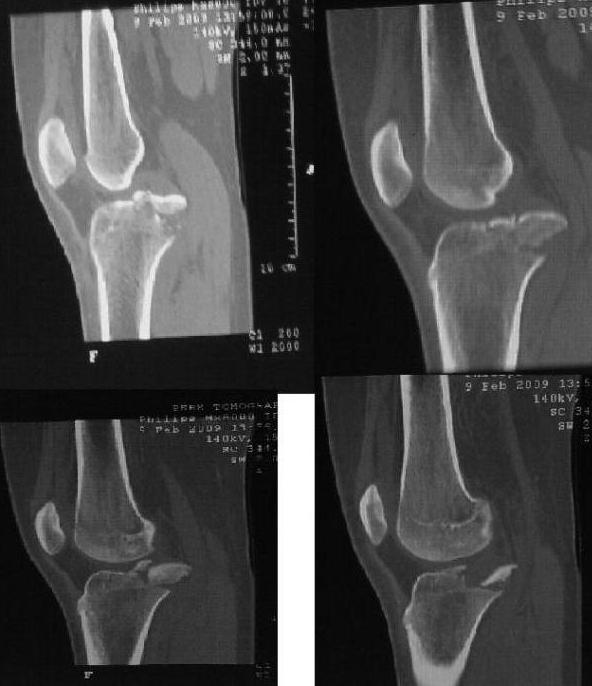

КТ мы конечно сделали, судя по результатам смещение довольно большое и оставить его без репозиции не представляется нам возможным. Планируем артротомию задним доступом и фиксацию фрагмента винтом или проволочным швом. Артроскопа не имеем.

Имя     : IMAG071812.jpg